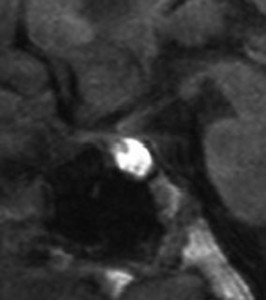

増大しても下垂体症状を出さなかった例

9歳の女の子に偶然発見された腫瘍です。何の症状もありませんでした。頭蓋咽頭腫と診断されて経過観察となりました。1年半観察しましたが腫瘍は増大して,視交差の変形が増して両耳側1/4半盲となり症候性となりました。下垂体機能は正常でした。

上のT2強調画像では,全体的に低信号で,高信号の部分が混在します。上右のCISS画像では,下垂体組織が右に変移していることが推定されます。

左がT1強調画像で高信号,右がT1ガドリニウム増強像ですが腫瘍は増強されません。正常か錐体が腫瘍の右側にくっついていて,ガドリニウム増強されています。典型的なトルコ鞍部黄色肉芽腫です。画像診断で,下垂体腺腫の腫瘍内出血とよく間違われるのですが,高信号になるのはコレステリン結晶を豊富に含むからです。ガドリニウム増強される部分がほとんどないという所見が頭蓋咽頭腫とは異なるところでしょう。